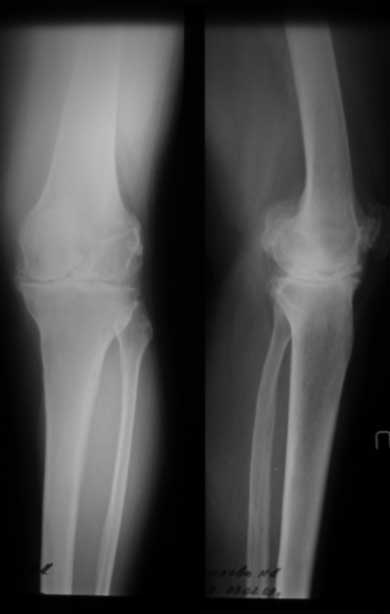

Уважаемые коллеги, как боретесь с ригидным коленом в положении разгибания при эндопротезировании? Пациентка 67 лет, ригидное колено в положении полного разгибания с качательными движениями до 5 град. Прооперировали внутренним доступом с отсечением бугристости. Сгибание до рефиксации бугристости - до острого угла, после максимум с/р 20-25/0/0. Выполнили миолиз доступных отделов 4-х главой мышцы бедра из доступа без особого результата. Основная проблема была в разгибательном аппарате, как с этим боретесь? До эндопротезировыания или после - полноценные операции на разгибательном аппарате как при контрактурах. P.S. снимки выложу чуть позже (не могу добиться нормальных проекций), грубых косяков пока не заметил (увеличенный offset и т.д.) С уважением Максим Агалаков, Е-бург

Разгибетельная контрактура нехарактерна для первичного гонартроза. О фактах травмы, иммобилизации, спастике разгибательного аппарата вы ничего не сказали.

По данным R-грамм, хотя качество их не очень..., мне кажется имеется 2 основных ошибки: 1. высокий уровень остеотомии большеберцовой кости, при разгибетельных контрактурах его необходимо делать ниже.